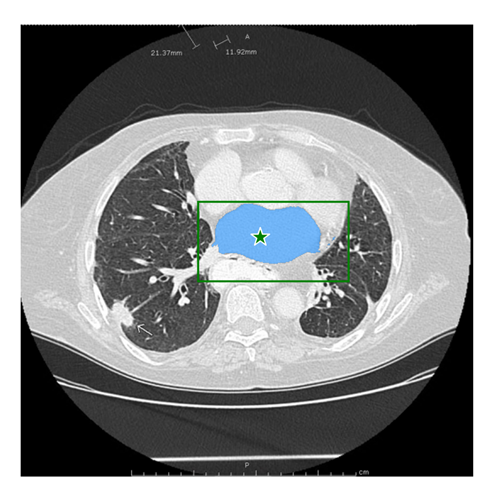

医学图像:

该图片是测试图片,从网站上下载的。